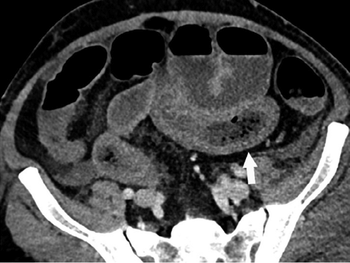

A five-tiered approach to cross-sectional interventional procedures can help radiologists determine which patients to treat first, minimizing likelihood of viral transmission.